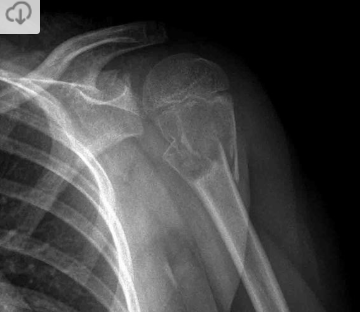

Condroblastoma da escápula